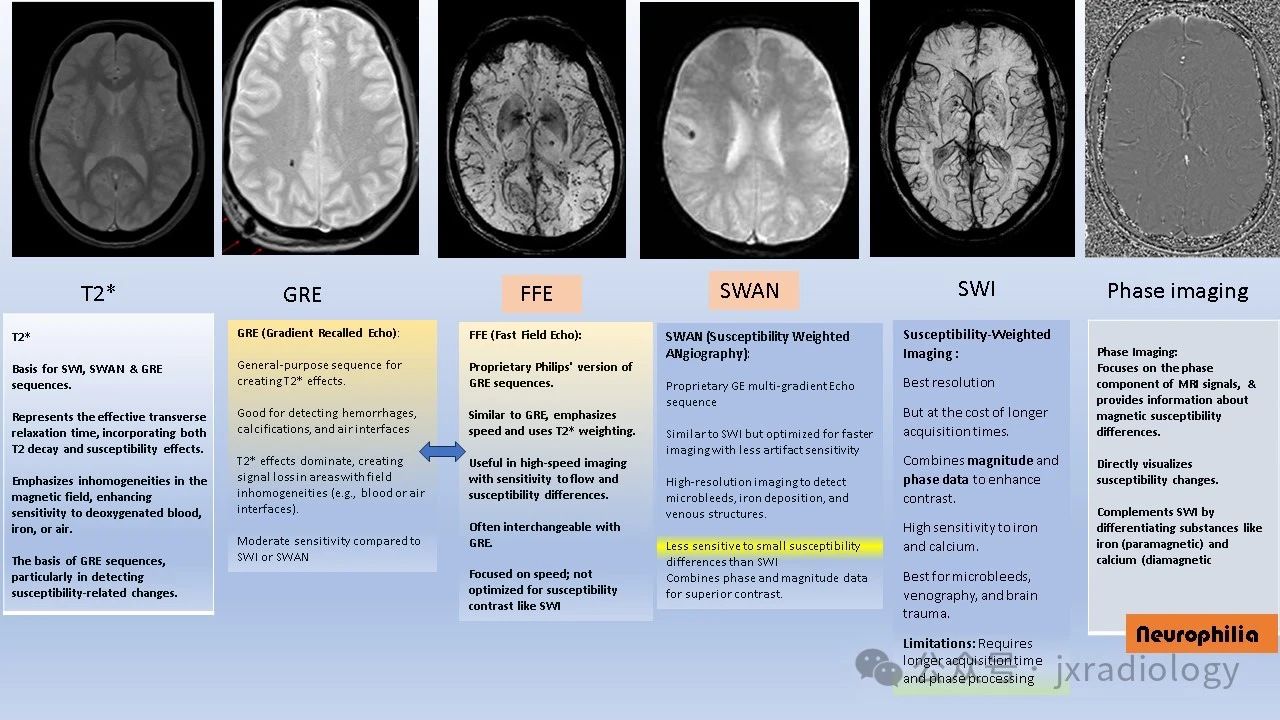

这张图是为非放射科医生设计的MRI参考指南,主要解释了T2*、GRE、FFE、SWAN、SWI和相位图等技术的基本概念。这几个序列是检测和评估顺磁性物质(如铁沉积、微出血)和抗磁性物质(如钙化)的关键工具。这些序列通过放大磁场不均匀性造成的信号变化,能够在微观层面揭示组织的生化和病理特征。

适用场景及临床价值:

T2*加权成像

• 是SWI、SWAN和GRE序列的基础。

• 反映了横向有效弛豫时间,结合T2衰减和磁敏感效应。

• 强调磁场中不均匀性的成像,增强对去氧血、铁或气体的敏感性。

• 是GRE序列的基础,特别是在检测与磁敏感相关的变化方面。

GRE(梯度回波)

• 一种通用的的GRE序列,用于创建T2*效应。

• 擅长检测出血、钙化和气体界面。

• T2*效应占主导,在磁场不均匀区域(如血液或气体界面)信号丢失较明显。

• 敏感性中等(与SWI或SWAN相比)。

FFE(快速场回波)

• 飞利浦公司的专有GRE序列版本。

• 与GRE类似,强调成像速度并利用T2*加权。

• 在快速成像中有用,针对流动和磁敏感差异的灵敏度较高。

• 通常与GRE互换使用。

• 专注于速度,但不像SWI那样优化磁敏感对比。

SWAN(磁敏感加权血管成像)

• GE公司专有的多梯度回波序列。

• 类似于SWI,但优化了成像速度,降低伪影敏感性。

• 高分辨率,可检测微出血、铁沉积及静脉结构。

• 对微小磁敏感差异的灵敏度低于SWI。

• 结合相位和幅度数据以获得更好的对比度。

SWI(磁敏感加权成像)

• 分辨率最佳。

• 但成像时间较长。

• 结合幅度和相位数据以增强对比。

• 对铁和钙非常敏感。

• 可用于检测微出血、静脉解剖及脑外伤。

• 限制:需要更长的扫描时间和后期处理。

相位图

• 专注于MRI信号的相位分量,提供关于磁敏感差异的信息。

• 可直接显示磁敏感变化。

• 补充SWI,能够区分铁(顺磁性)和钙(抗磁性)等物质。根据不同厂家左右手规则决定信号特点。

• 优点:增强对磁敏感变化的直接可视化。

实用指南:

• 对于大多数应用,SWAN和GRE即可满足需求,因其成像时间较短。

• 如果需要高分辨率的详细对比(如微出血的检测),SWI是最佳选择。

• 要区分铁和钙,建议选择相位成像,因为铁在所有序列中均为黑色,而钙在相位图中为白色(左手规则的设备)。

小知识:

• 类比“德国铁十字”,铁在GRE、SWAN、SWI和相位图中均显示为黑色。

• 钙和镁则如“阴阳”,在GRE/SWAN/SWI中为黑,在相位图中为白。

总结:选择序列取决于临床需求和MRI扫描仪的设置。复杂情况下,可咨询放射科医生以获得建议。